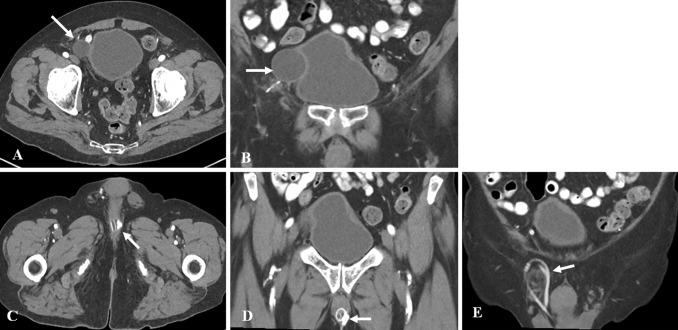

To discuss the imaging appearances of various pathologies affecting adult male urethra and to review the role of imaging in the assessment of artificial urinary sphincters and penile prostheses. Diagnosis of common male urethral diseases heavily depends on two conventional fluoroscopic techniques namely retrograde urethrography and voiding cystourethrography. These are useful in evaluating common urethral diseases like traumatic injury, infections, and strictures. Cross-sectional imaging can be useful in evaluating periurethral pathologies. Artificial urinary sphincters, slings, and periurethral bulking agents are used in the management of urinary incontinence and imaging can be utilized to detect complications in these devices. Cross-sectional imaging especially MRI plays a significant role in evaluating the different types of penile prostheses and their malfunctioning.

讨论影响成人男性尿道的各种病变的影像学表现,并回顾影像学在评估人工尿道括约肌和阴茎假体中的作用。常见男性尿道疾病的诊断主要依赖于两种常规的荧光透视技术,即逆行尿道造影和排尿性膀胱尿道造影。这些技术在评估外伤性损伤、感染和狭窄等常见尿道疾病方面非常有用。横断面成像可用于评估尿道周围病变。人工尿道括约肌、吊带和尿道周围填充剂用于治疗尿失禁,影像学可用于检测这些装置的并发症。横断面成像,特别是 MRI,在评估不同类型的阴茎假体及其故障方面发挥着重要作用。